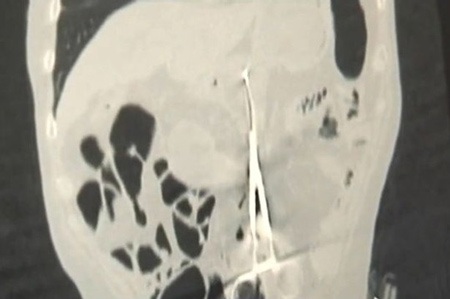

Báo Anh Mirror ngày 14/12 đưa tin ông Karp Ponomaryov, 53 tuổi đến từ Kazakhstan được phẫu thuật cứu mạng hơn 12 năm trước nhưng các nhân viên y tế đã mắc phải lỗi lầm nghiêm trọng: Để lại cây kéo phẫu thuật dài 20 cm trong cơ thể ông. Kể từ đó, người đàn ông này đau dạ dày dữ dội mỗi khi ăn no nhưng ông không bao giờ phàn nàn mà luôn cố gắng vui vẻ vì đã sống sót sau ca phẫu thuật. Tuy nhiên, cách đây 1 tháng, ông mất cảm giác ngon miệng, giảm cân nhanh nên tìm đến bác sĩ để chữa trị.

Bác sĩ Baurzhan Aybaev (44 tuổi) - người kiểm tra kết quả chụp X-quang cho Karp Ponomaryov - cho biết: “Tôi chưa bao giờ thấy bất cứ chuyện gì như thế này. Tôi đã từng thấy miếng gạc phẫu thuật hoặc các thiết bị nhỏ bị bỏ lại nhưng chúng được phát hiện sớm hơn. Có lẽ bệnh nhân đã chịu đau đớn rất nhiều”.